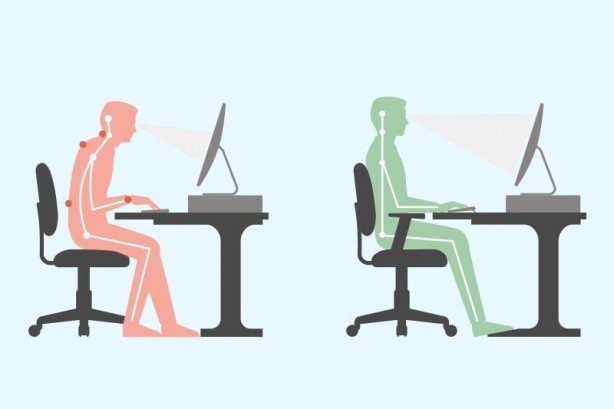

Duruş bozukluklarının fiziksel ve ruhsal olarak birçok soruna yol açabileceğini belirten Fiziksel Tıp ve Rehabilitasyon Uzmanı Dr. Esin Selimoğlu, yanlış duruş pozisyonlarının, boy kısalmasına dahi neden olabileceğini söyledi.